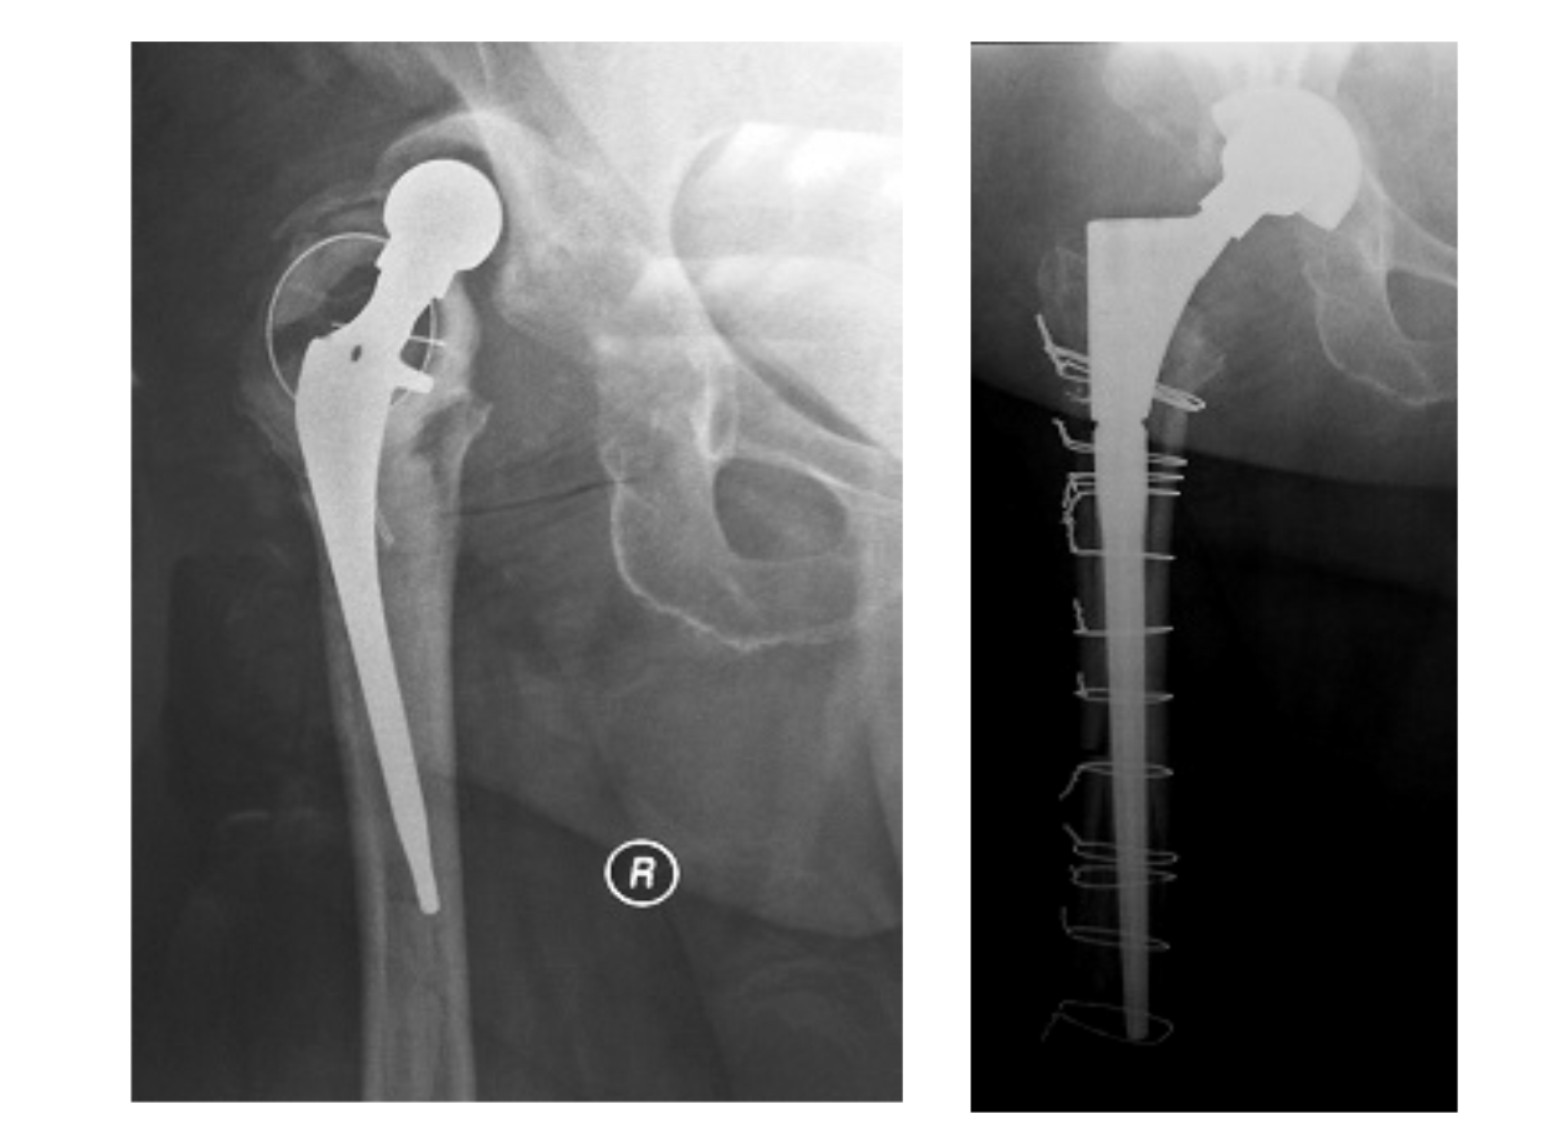

Στην εικόνα 2 ασθενής με πολλαπλά επεισόδια εξαρθρήματος και μία επέμβαση αναθεώρησης χωρίς επιτυχία ήδη στο ιστορικό του. Αιτία, δεν ήταν η κακή τοποθέτηση όπως αρχικά είχε θεωρηθεί, αλλά νευρομυικό πρόβλημα. Αντιμετωπίσαμε την κατάσταση με αναθεώρηση, χρησιμοποιώντας μια ειδικού τύπου κοτύλη, “κλειδούμενη”. Ο ασθενής έζησε άλλα 7 χρόνια μετά την επέμβαση,  με πλήρη δραστηριότητα, χωρίς να υποστεί ξανά εξάρθρημα